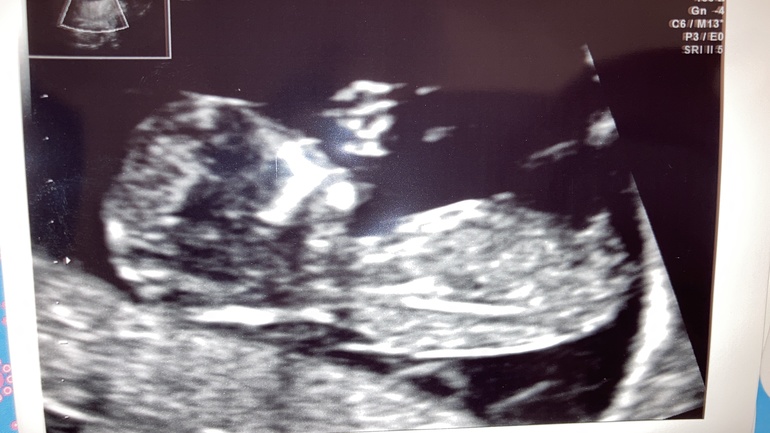

Во втором месте нужно было заранее сдать кровь на скрининг и после узи можно было сразу получить на руки рассчитанные риски. Малыш весь скрининг прятался куда-то вглубь, доктор сильно давил на живот датчиком и ещё и рукой с другой стороны, что бы подогнать ребёнка туда, куда нужно.😱 По скринингу все риски были очень низкие и доктор дал мне 93% гарантии, что малыш без патологий. Срок поставил почти на неделю больше, чем по м. Но я всё же настояла на нипте. Во время скрининга доктор показал мне срез между ножек малыша многозначительно кивнул. 😂 Пол он не имеет права говорить до 14 недель, но было видно, что это мальчик.😍

7.01.21 ( 14+6/15+4) я была на плановом приёме у новой гинеколога, она делала цервикометрию и сказала, что может сказать пол малыша, т.к. очень уж хорошо он лежит- всё как на ладони.😁 Тут я уже не устояла и она подтвердила, что у меня в животике сынок.😍